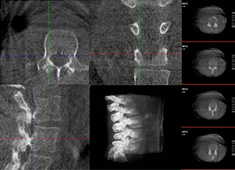

術(shù)中三維CT如何輔助手術(shù)機(jī)器人完成手術(shù)導(dǎo)航

手術(shù)機(jī)器人對(duì)術(shù)中配準(zhǔn)的要求較高,僅依靠其自身的導(dǎo)航定位功能還遠(yuǎn)遠(yuǎn)不夠,需要結(jié)合術(shù)中三維CT影像來提高導(dǎo)航精準(zhǔn)度。術(shù)中三維CT是如何輔助手術(shù)機(jī)器人完成手術(shù)導(dǎo)航的?下面以術(shù)中三維移動(dòng)C臂(PLX C7600)輔助脊柱外科手術(shù)...